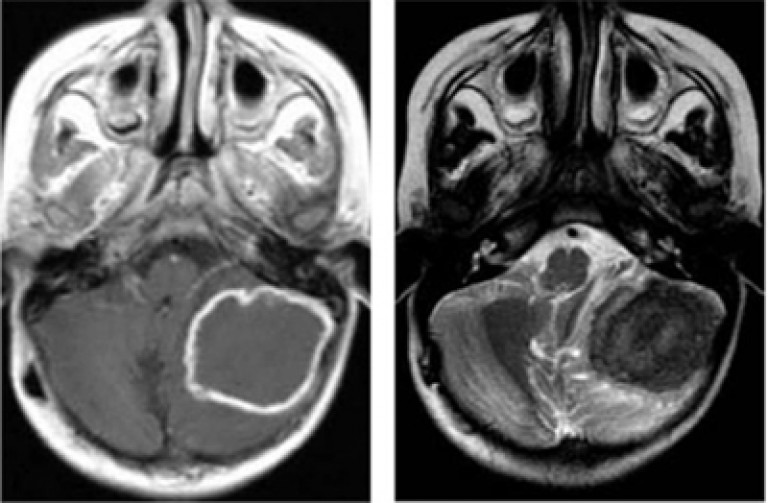

При МРТ и КТ

обнаруживаются многочисленные мелкие очаги инфарктов.

При МРТ и КТ у больных паренхиматозным нейросифилисом обнаруживают атрофию лобных и теменных долей, расширение желудочков головного мозга, множественные мелкие очаги инфарктов в полушариях большого мозга и мозговом стволе.